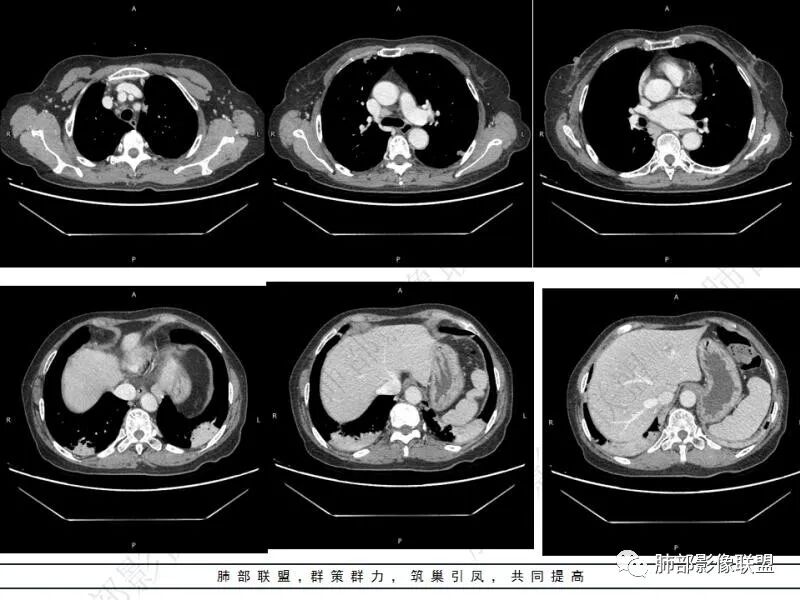

songml:老年女性,结肠癌术后,下腹隐痛。双肺胸膜下散在结节影,大小不一,下肺为著,肺野清晰,实变结节有强化,有毛毛征。考虑隐球菌感染。

谢加平:结肠癌术后史,两肺胸膜下多发结节及斑块实变病灶,实边边界平直征(亚急性和慢性病变过程),双肺下叶后基底段胸膜下为甚,与胸膜平行特点,见支气管充气征,边缘模糊的GG0,首诊2022年11月18日肺部CT,与治疗11月28日对比,病灶未吸收,双肺下叶胸膜下病灶有侧向融合特点,综合分析符合炎性肉芽肿,隐球菌感染。

老年女性,结肠癌术后。两下肺胸膜下为主片状实变,右下肺短期复查融合且病灶长轴平行于胸膜,实变内可见支气管充气征,边缘磨玻璃晕,另两肺内胸膜下散在数枚小结节状、楔形实性灶。考虑感染性病变,隐球菌可能,鉴别肺转移。

2.影像特征:双肺胸膜下多发实性结节、磨玻璃影及实变影,胸膜下优势分布、晕征、胸膜下脂肪间隙存在,部分病灶边界平直征,有侧向融合趋势。

3.CEA复查1.8ng/ml,常规情况,基本排除转移。广谱抗生素治疗后无效,病灶仍然进展,考虑特殊感染。